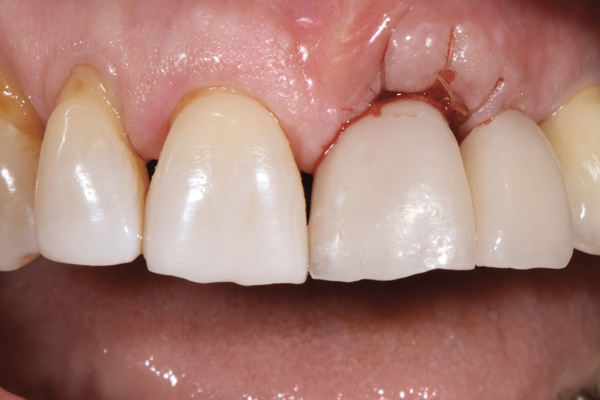

Fig 3. Placement of abutments that create blanching of the peri-implant soft tissue will result in unpredictable remodeling of the tissue to a more apical position, which may create an esthetically displeasing result. This is best managed in the esthetic zone by shaping the soft tissue in the provisional stage rather than with the definitive abutment.

Figure 3